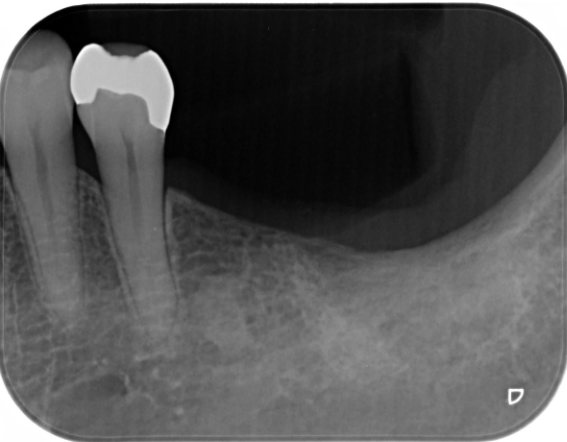

症例3

| 項目 | 詳細 |

|---|---|

| 患者様データ | 50代 男性 |

| 来院時の主訴 | 「左下で噛むと違和感がある。」 |

| 医院の診断 | 左下第二大臼歯の歯根破折 |

| 通院期間 | 9か月 |

| 来院回数 | 12回 |

| 治療費 | 総額:835,000円(税抜) 【内訳】 インプラント埋入手術250,000円、GBR(骨再生手術)150,000円、2次手術+FGG(遊離歯肉移植術)55,000+60,000円、仮歯30,000円、インプラント上部構造(セラミッククラウン)170,000円、隣在歯セラミッククラウンのやりかえ120,000円 |

| リスクと副作用 | 定期的なメンテナンスが必要、術後若干の腫れと痛み |

| ここがこだわりのポイント!☝ | インプラント周囲に角化歯肉と言われる健常な歯肉がなかったので、口蓋からの歯肉移植を行っています💡この角化歯肉がないと、インプラントをしてもうまく歯磨きができないことがあります。 |